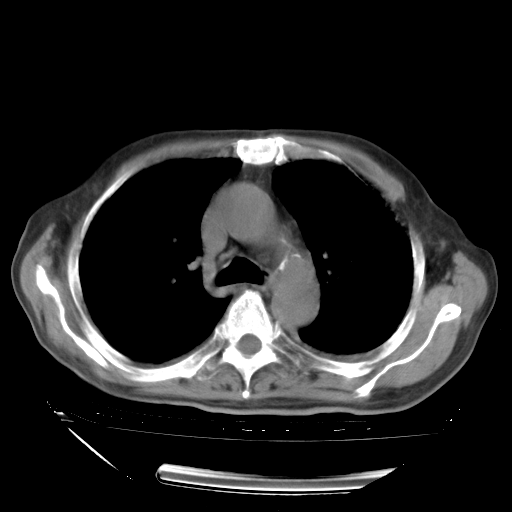

经过24天治疗,岳父的病情基本稳定。生活基本可以自理,可以下床活动。呼吸困难早已消失。体温基本正常。

只是甲强龙用80mg时血小板升到正常,改为60mg后又降到63×10*9/L。

主要治疗甲强龙80mg×14天,60mg×10天;同时抗结核(异烟肼+利福平+乙胺丁醇)。环磷酰胺0.1 tid 10天。

特别感谢胡教授、高管、桃子版主给出关键的治疗建议。桃版把所有肺部影像和全部临床资料请所在医院呼吸科、感染病科、结核科、临床免疫科专家会诊。临床免疫科专家制定了完整的治疗方案。

下一步治疗强地松+环磷酰胺+抗结核。 |